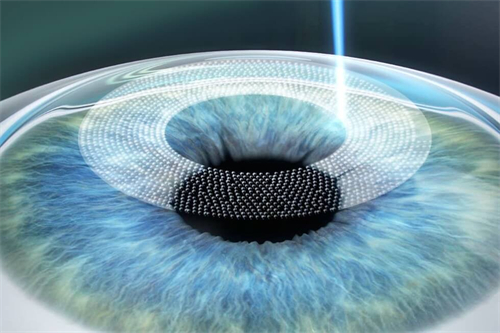

首先,需要明确的是,高度近视1500度并非手术的肯定禁忌。在医学技术不断发展的今天,有多种手术方式可以考虑用于矫正高度近视。其中,眼内屈光手术,特别是人工晶体植入术(ICL),被认为是针对高度乃至***度近视患者的有效选择。

人工晶体植入术(ICL)通过在眼内植入一个特殊的人工晶体来矫正视力,这种手术避免了切削角膜的风险,且对角膜厚度没有严格要求。对于近视度数高达1500度的患者来说,这种手术方式可能更为适合。ICL手术适应的近视度数范围广泛,通常可矫正300度到2300度的近视,以及600度以下的散光。

然而,手术并非一蹴而就。在决定进行手术之前,患者需要进行多方面的眼部检查和评估。医生会对患者的角膜厚度、眼底情况、视网膜健康状态等进行详细检查,以评估手术的风险和可行性。这些检查有助于医生确定适合患者的手术方式和术后护理方案。